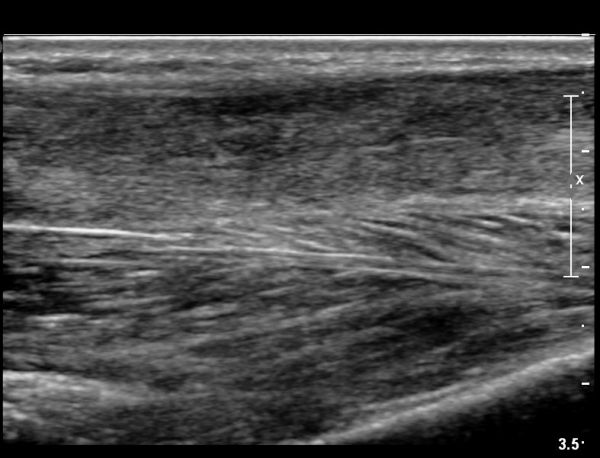

2018³â  1¿ù 30ÀÏ ÃßÀû°Ë»ç

¾ÆÅ³·¹½º°Ç Àú¿¡ÄÚºÎÁ¾ÀÌ °¨¼ÒµÇ°í  ÆÄ¿­ºÎÀ§ Àú¿¡ÄÚ°¡ È£ÀüµÇ¾î

°ÇÀÇ ¼¶À¯¼º¾ç»ó(fibrillar pattern)ÀÌ È¸º¹µÇ°í ±¹¼ÒÀû ¿¬°á¼º ¼Ò½ÇÀÌ »ç¶óÁü(»çÁø 9, 10, 11, 12).